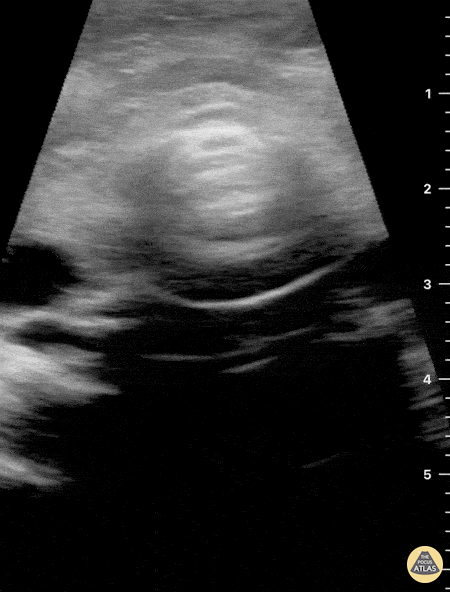

12 hours after having a fall in her bathroom, an otherwise healthy 54 y/o female presented to the ED complaining of neck pain, dysphonia and difficult swallowing. Physical examination revealed hypertension, a HR of 109 bpm (sinus tachycardia) and 98% environmental O2Sat. She had no trouble breathing or speaking, although a coarse tone of voice was evident. Her skin revealed a mild linear abrasion with local upper right lateral neck swelling. A firm, tender submandibular mass was palpable. Neck ultrasound seen here revealed the trachea in a central position and the carotid arteries with no obvious signs of injury. Jugular vasculature was also studied and showed no adjacent fluid collections (not visualized in this clip). Sliding the probe to the right submandibular region revealed a well defined hypoechoic structure compatible with an enlarged salivary gland. Dr. Felipe Urriola & Dra. Daniela Gallardo Emergency Unit, Puerto Aysen Hospital. Chilean Patagonia